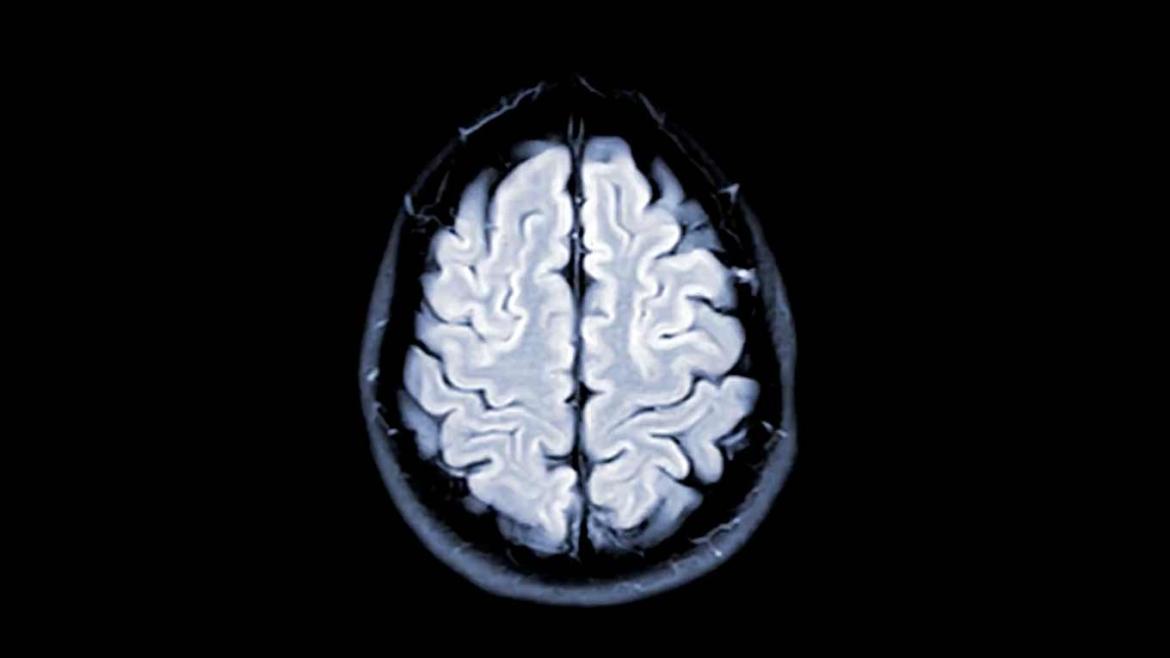

For adults in midlife, difficulty getting to sleep and waking up too early may accelerate brain atrophy that is associated with dementia.

The brain naturally begins to atrophy beginning in one’s 30s and 40s. But this can become much more pronounced with dementia and disorders like traumatic brain injury, stroke and, in some cases, multiple sclerosis.

The researchers used machine learning, leveraging data from the scans, to estimate the brain age of each participant based on the actual degree of brain shrinkage. They found that even after adjusting for age, sex, education, health and lifestyle factors, the brains of those participants who slept poorly were more atrophied than those who slept well.

Compared to the 70% of the sample who reported having little trouble sleeping, those with moderate difficulty (22%) had brains that were 1.6 years older, while those with the most difficulty (8%) had brains that were 2.6 years older.